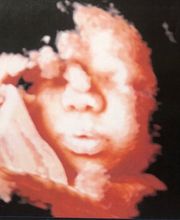

Lo studio medico Sciuto, rivolgendosi alle pazienti con professionalità e disponibilità, si occupa della cura e del trattamento delle problematiche ginecologiche ed ostetriche impiegando adeguate strumentazioni diagnostiche. Prestazioni e servizi: - Visita ginecologica e senologica; - Ecografia ostetrica; - Ecografia ginecologica (transaddominale e transvaginale); - Diagnosi prenatale: - Colposcopia; - Pap test; - Tamponi vaginali; - HPV-DNA test; -Cryo conservazione delle cellule staminali del cordone ombellicale; -Cardiotocografia. Lo studio medico Sciuto si trova al centro di Catania in Via Agostino De Cosmi,5. Si riceve solo su appuntamento.